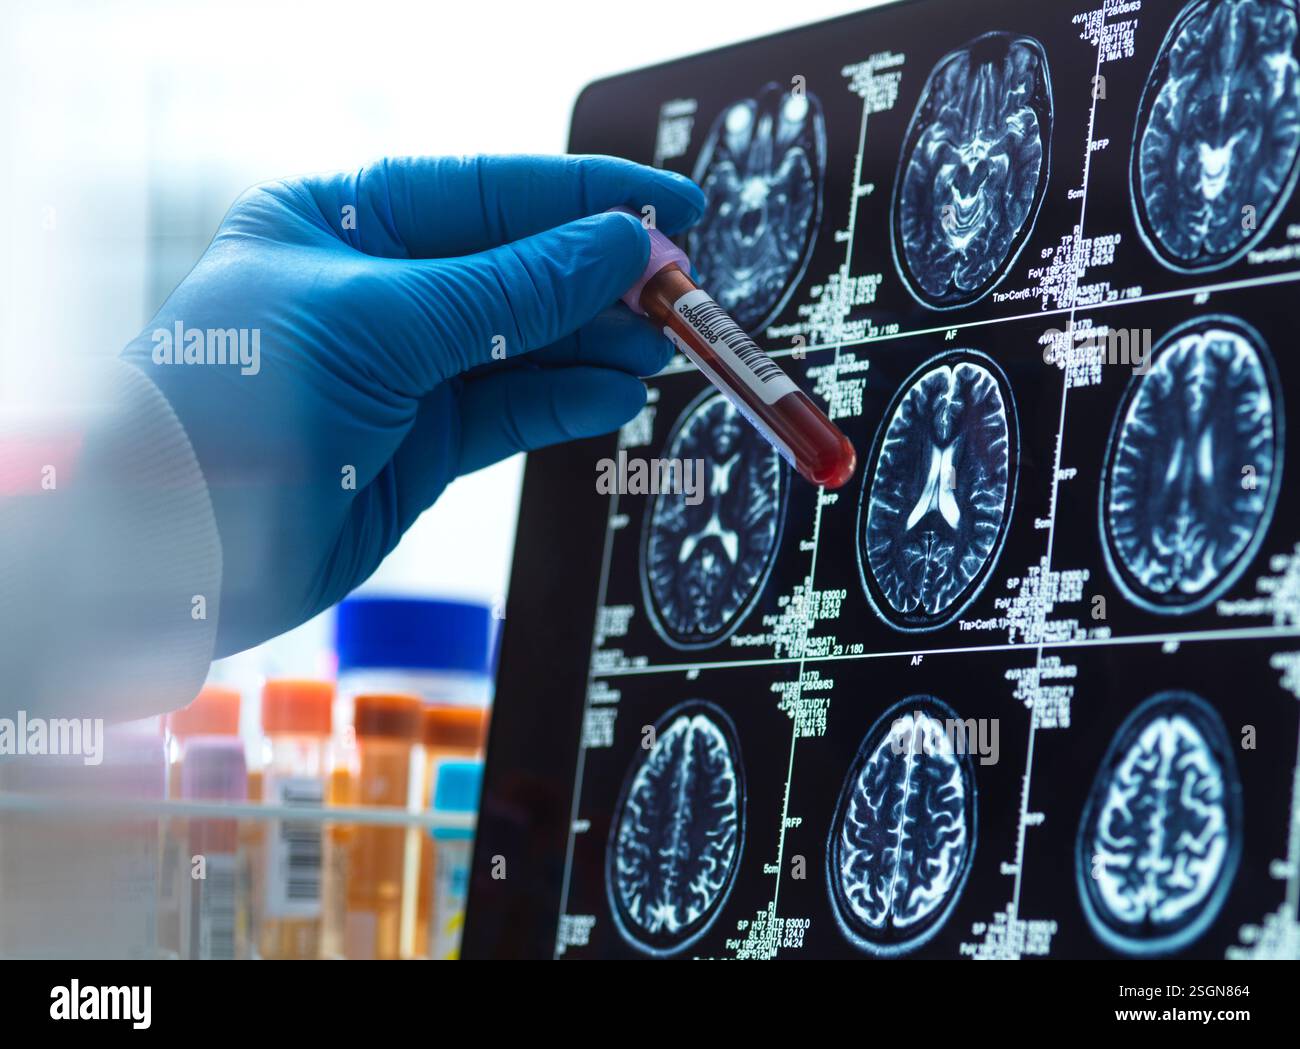

Neurology Research,Patients blood sample being checked against the medical scan during a clinical trial Stock Photohttps://www.alamy.com/image-license-details/?v=1https://www.alamy.com/neurology-researchpatients-blood-sample-being-checked-against-the-medical-scan-during-a-clinical-trial-image647084814.html

Neurology Research,Patients blood sample being checked against the medical scan during a clinical trial Stock Photohttps://www.alamy.com/image-license-details/?v=1https://www.alamy.com/neurology-researchpatients-blood-sample-being-checked-against-the-medical-scan-during-a-clinical-trial-image647084814.htmlRF2SGN77X–Neurology Research,Patients blood sample being checked against the medical scan during a clinical trial